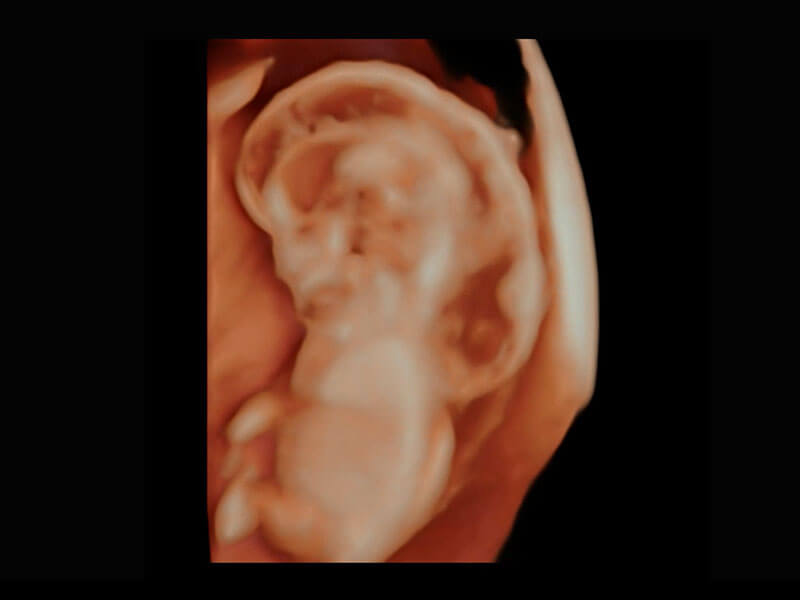

中晚孕筛查

P60提供简单易学易用的高端诊断工具,为您中晚孕筛查提供快速清晰的解剖信息。